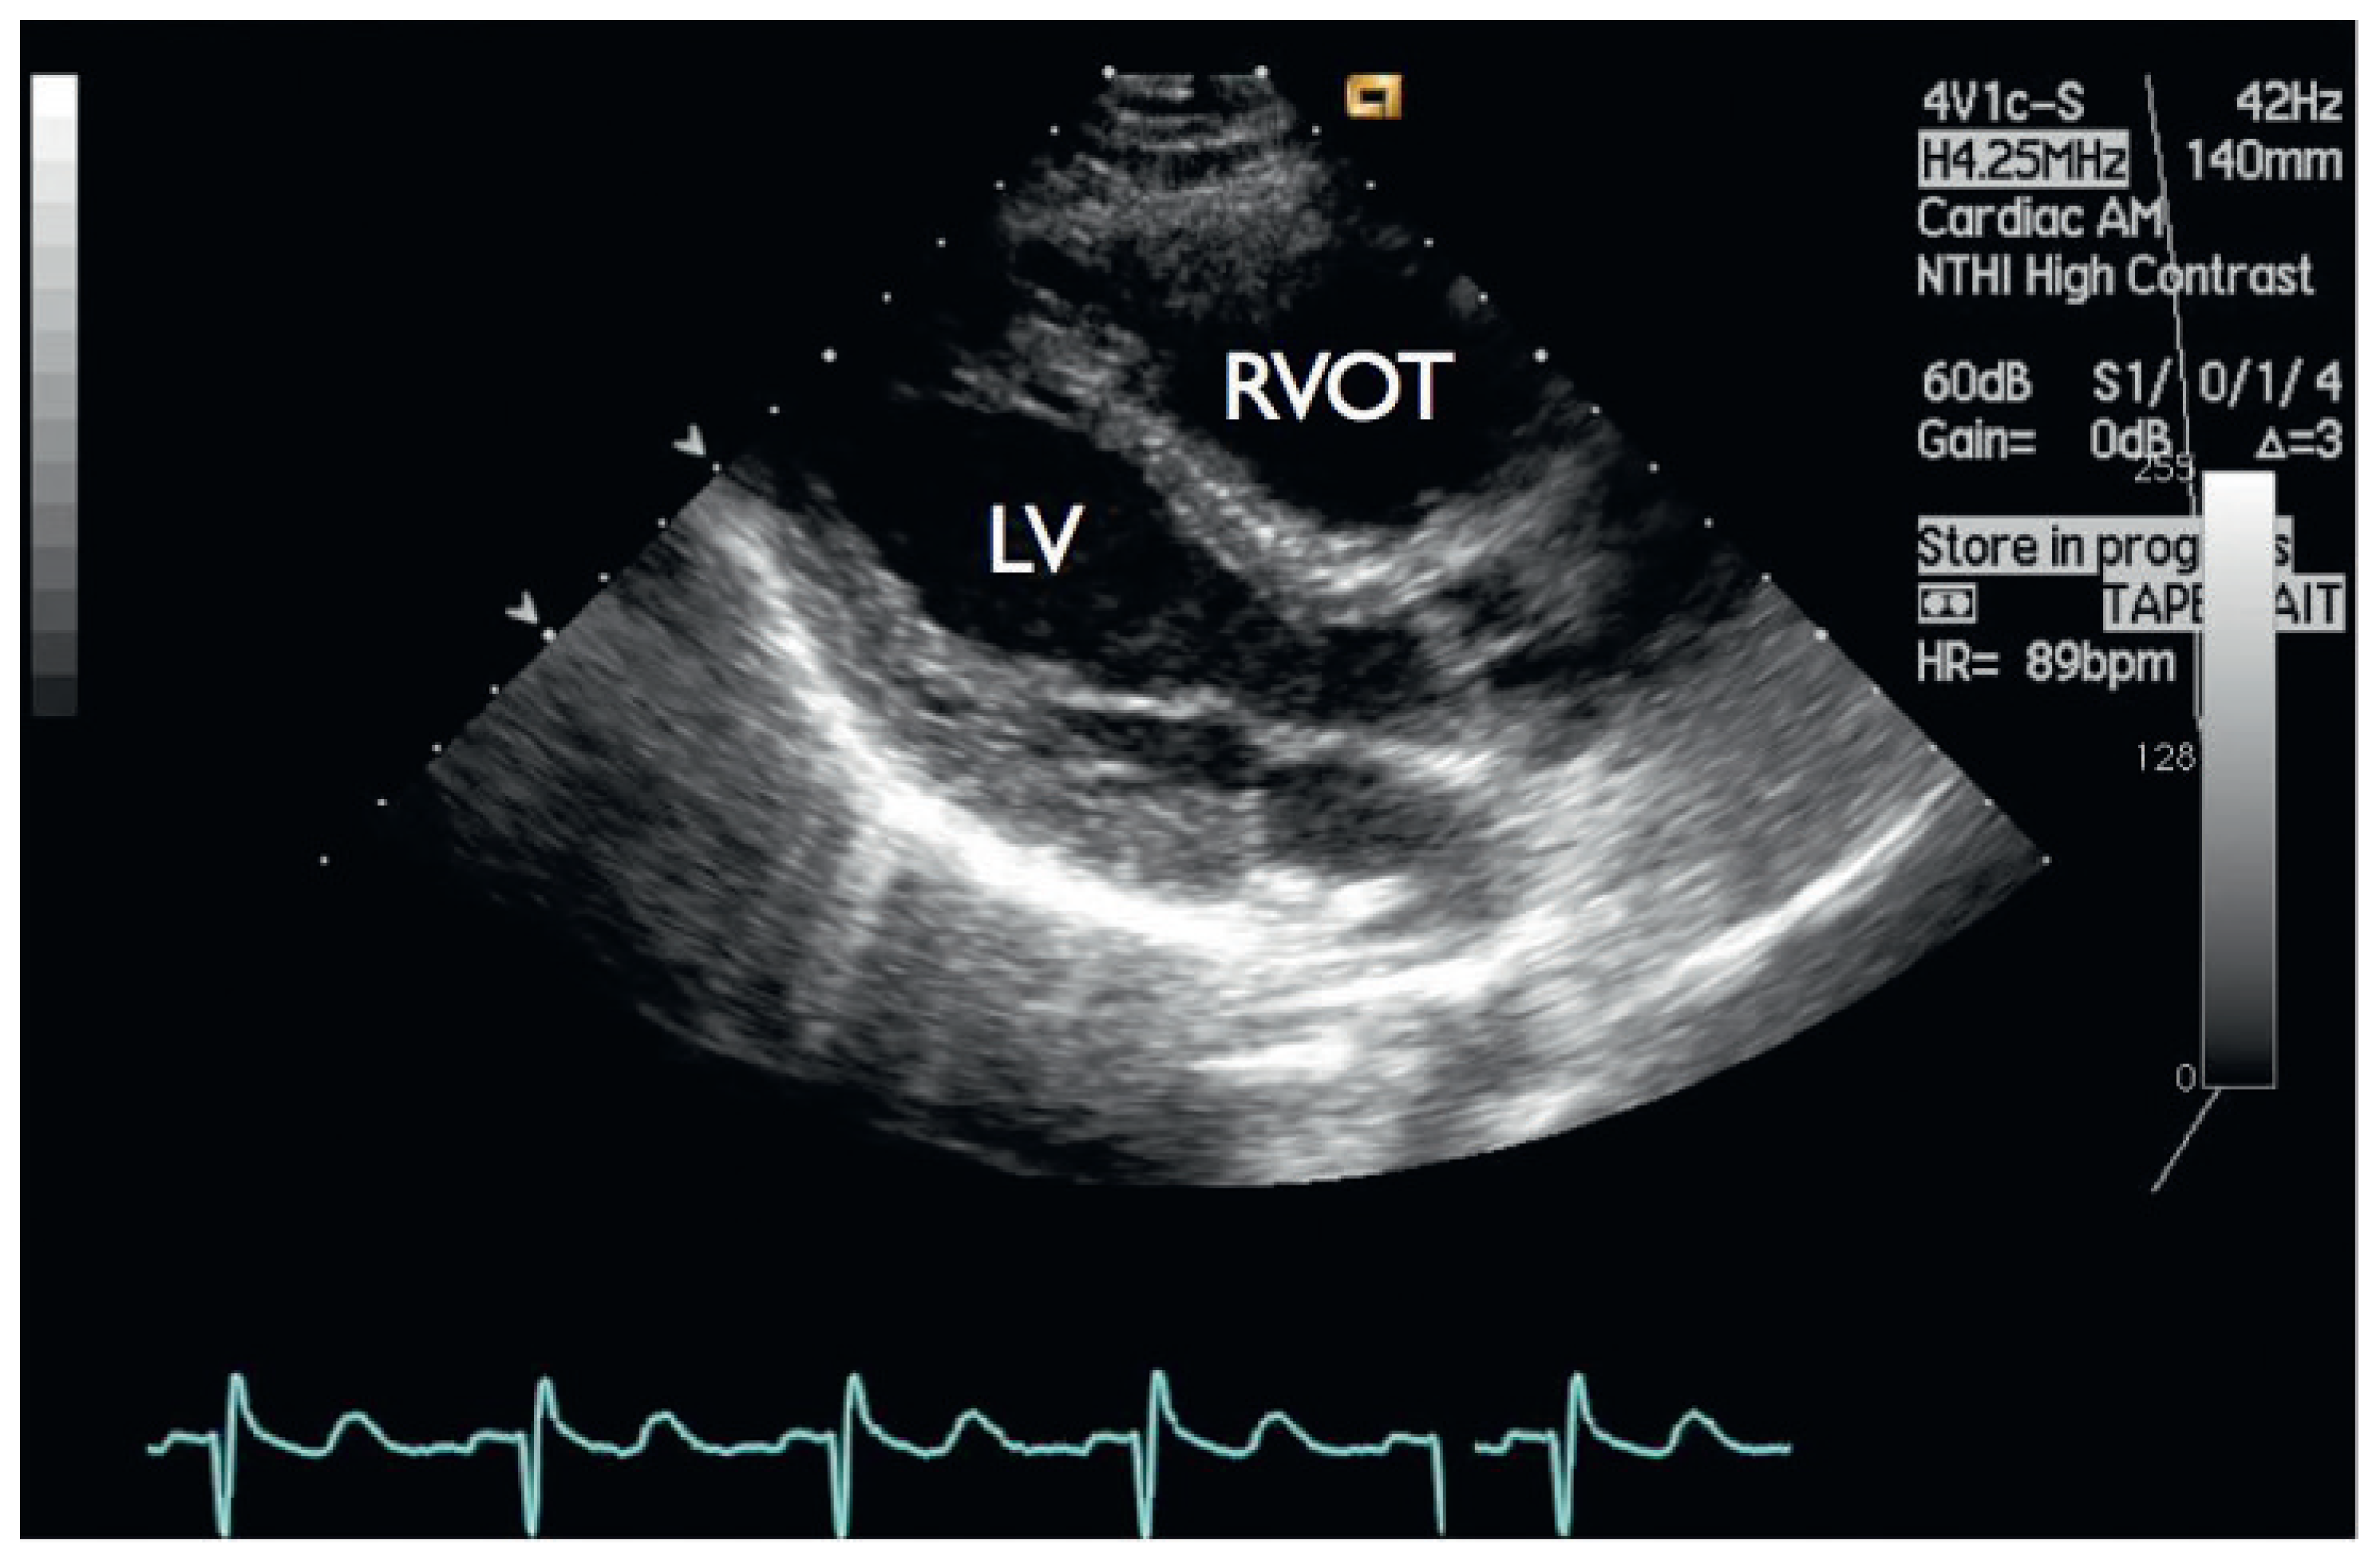

Typical Signs of Secundum Atrial Septal Defect in a Young Man

Case report